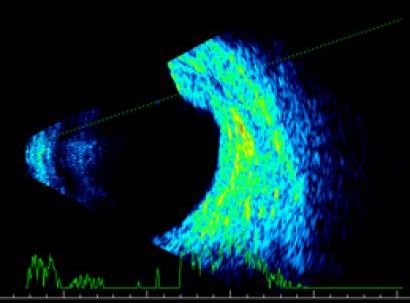

Примеры патологий при Б-сканировании

![]() |

| Меланома сосудистой оболочки | Эндофтальмит |